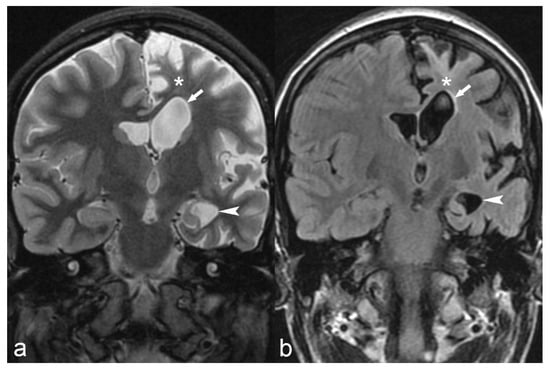

Figure 12.

18-year-old female with medically refractory epilepsy. Coronal T2 (a) and FLAIR (b) images show hemispherical parenchymal volume loss and cortical thinning (asterisk) on the left side with resultant ex vacuo dilatation of the frontal (arrow) and temporal horns (arrowhead) of the left lateral ventricle, consistent with Rasmussen’s encephalitis.

Rasmussen’s encephalitis is a rare syndrome of unknown etiology, probably immune-mediated, often presenting with drug-resistant epilepsy at childhood. MRI in Rasmussen’s encephalitis reveals progressive atrophy of one of the cerebral hemispheres (Figure 12), usually beginning in the opercular region [22]. Often, the cortex and subcortical white matter present hyperintense signal on T2WI and FLAIR [22].